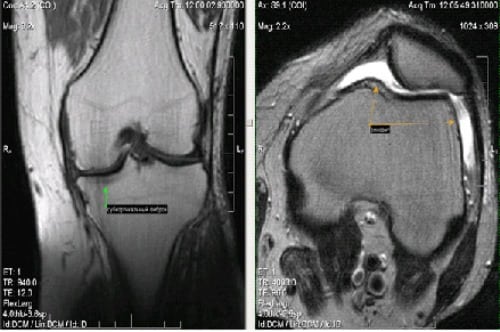

Диагноз выставляется на основании жалоб пациента, внешнего осмотра, результатов инструментальных исследований — рентгенографии, КТ, МРТ, при необходимости — артроскопии. При подозрении на инфекционную этиологию синовита проводятся бактериологические анализы. Лечение острой и подострой формы заболевания консервативное. Хронический рецидивирующий синовит требует хирургического вмешательства.

Инструментальные исследования необходимы не только для установления стадии патологии, количества развившихся осложнений, но и для выявления причины патологии. Проводятся следующие диагностические мероприятия:

- МРТ, КТ, при необходимости — рентгенография.